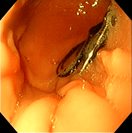

‣当院での症例紹介

異物:1円玉

異物:裁縫針

異物:梅干しの種

胃腺癌

胃瘻チューブ設置

炎症性ポリープ

炎症性ポリープ⑵

気管虚脱

気管支腫瘍

気管腫瘍

喉頭腫瘍

食道内異物回収後

鼻腔内腫瘍(犬)

鼻腔内腫瘍(猫)

慢性腸症(犬)

慢性腸症(猫)